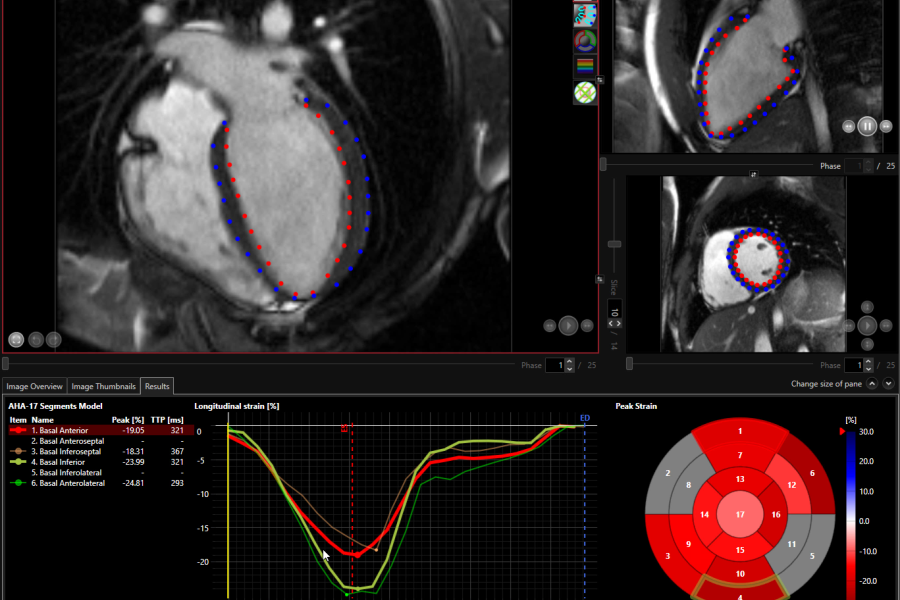

• Three strain types are determined: longitudinal, circumferential, and radial;

• Global Longitudinal Strain including Peak Strain (%) and Time to Peak Strain (ms);

• AHA 17 segment model including strain type choice;